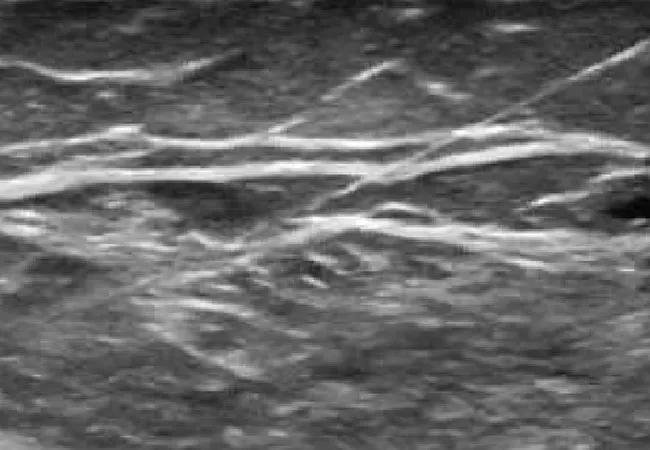

Figure 2. Ultrasound imaging during gastrocnemius muscle injection, allowing precise needle placement (needle is shown entering from the upper right corner).

Ultrasound provides information about muscle size and fibrosis, both of which can be important factors in decision-making. The modality also enables the operator to directly visualize the entire process, including needle placement. This allows the operator to gain a better understanding of the individual’s anatomy while performing the injection, facilitating target selection and further improving injection technique (Figure 2).